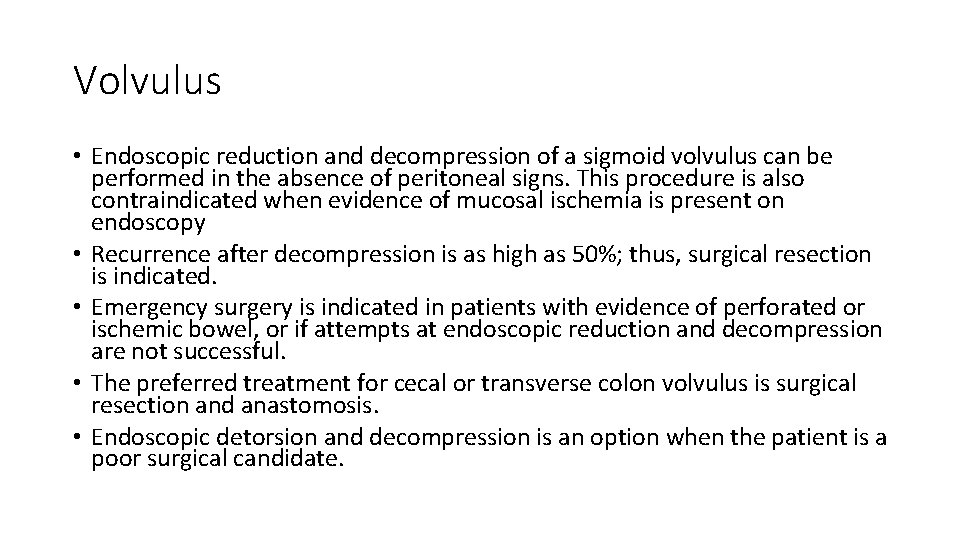

Volvulus • Endoscopic reduction and decompression of a sigmoid volvulus can be performed in the absence of peritoneal signs. This procedure is also contraindicated when evidence of mucosal ischemia is present on endoscopy • Recurrence after decompression is as high as 50%; thus, surgical resection is indicated. • Emergency surgery is indicated in patients with evidence of perforated or ischemic bowel, or if attempts at endoscopic reduction and decompression are not successful. • The preferred treatment for cecal or transverse colon volvulus is surgical resection and anastomosis. • Endoscopic detorsion and decompression is an option when the patient is a poor surgical candidate.